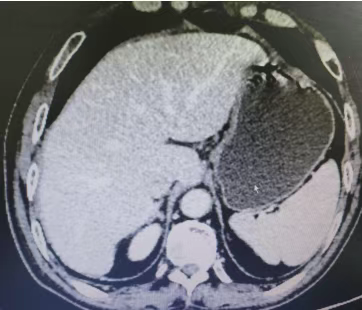

Abdominal CT films (2 sheets) on August 13, 2019